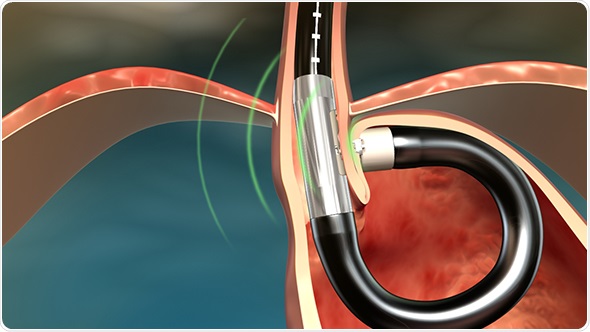

Its platform consists of a single use flexible surgical endostapler, equipped with a proprietary miniature camera, an ultrasonic sight and a range finder, and includes a handle with controls, an 80cm flexible shaft, a 5cm rigid section holding a cartridge with 5 standard 4.8mm titanium surgical staples, a ratchet controlled one-way articulating section, and a distal tip.

The MUSE endostapler is progressed into the stomach through an overtube and retroflexed under direct video guidance. After identifying an ideal stapling location, the stapler is gently pulled back to place the staple cartridge in the lower esophagus approximately 3cm above the gastroesophageal junction. The procedure typically delivers about five staples to effectively reinforce the LES.

The device’s video camera offers direct visualization during insertion and staple site selection, and ultrasound to determine when a proper stapling gap is achieved.